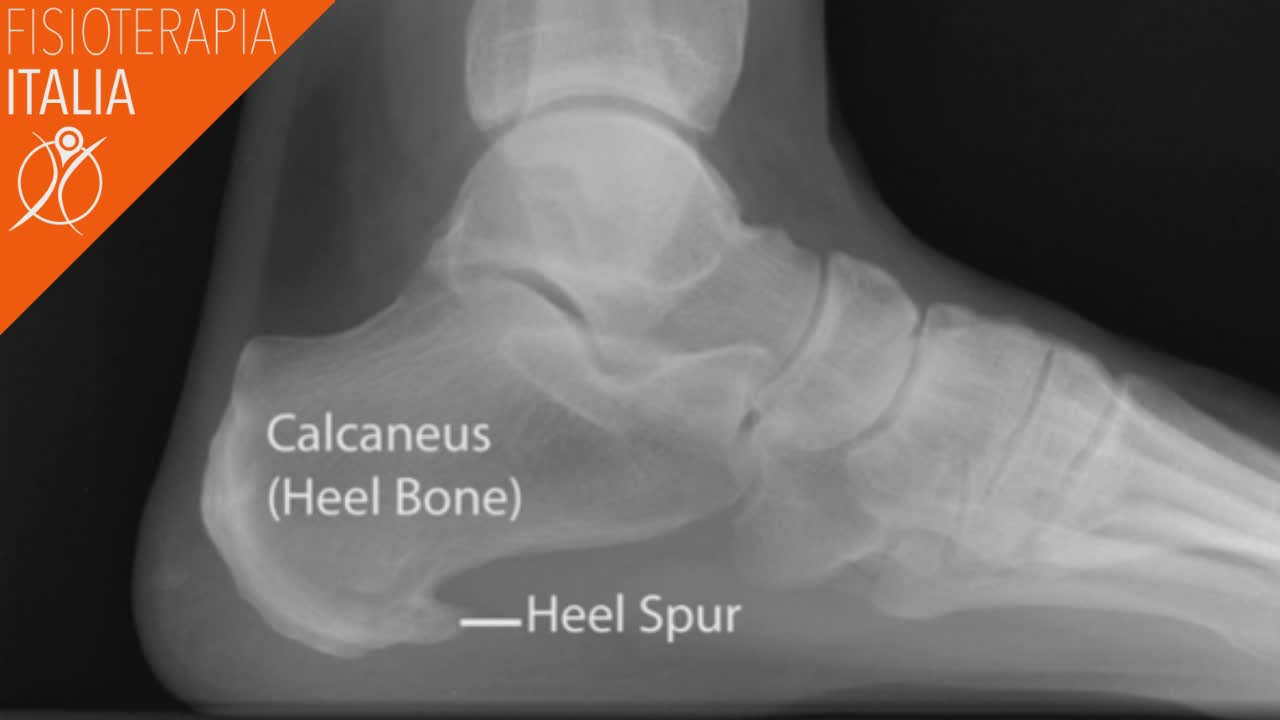

Spina calcaneare

Una spina calcaneare, o sperone calcaneare, è una crescita di calcio che si sviluppa tra l'osso del tallone e l'arco del piede, molto spesso associata alla fascite plantare. Per molte persone, non ci sono sintomi ma, per altri, può rappresentare una condizione dolorosa e causare infiammazione nei tessuti molli circostanti. Questa patologia non può essere facilmente diagnosticata e richiede un esame diagnostico come Raggi X o risonanza magnetica. La spina calcaneare si presume sia causata da tensioni e sovraccarichi dei tessuti molli. Può anche essere provocata da malattie auto immuni come l’artrite, eccesso di peso corporeo o l’utilizzo di calzature inadatte. I sintomi della spina calcaneare possono includere:

Se una persona manifesta questi sintomi, un medico eseguirà una radiografia del piede per determinare la causa del problema. Vedere la sporgenza su una radiografia è l'unico modo per essere sicuri che una persona presenti una spina calcaneare.

Questa condizione potrebbe, in alcuni casi, essere asintomatica. A volte il paziente scopre la presenza di una spina calcaneare tramite una radiografia effettuata per un altro motivo.

Uno sperone calcaneare o spina calcaneare, è una crescita di calcio che si sviluppa tra l'osso del tallone e l'arco del piede, molte volte associata alla fascite plantare. Per molte persone, non ci sono sintomi ma, per altri, può rappresentare una condizione dolorosa e causare infiammazione nei tessuti molli circostanti. Questa non è una patologia che può essere facilmente diagnosticata e richiede un esame diagnostico come l’Rx o la Risonanza Magnetica per una conferma.

La spina calcaneare si presume che sia causata da tensioni e sovraccarichi dei tessuti molli. Possono anche essere causati da malattie auto immuni come l’artrite, eccesso di peso corporeo o dal fatto di indossare calzature inadatte. I sintomi della spina calcaneare possono includere:

Se una persona manifesta questi sintomi, un medico può eseguire una radiografia del piede per determinare il problema. Vedere la sporgenza su una radiografia è l'unico modo per essere sicuri che una persona presenti speroni calcaneari.

Questa condizione potrebbe, in alcuni casi, essere asintomatica. A volte il paziente scopre la presenza tramite una radiografia effettuata magari per un altro motivo. I trattamenti possono includere un impacco freddo, iniezioni di farmaci antinfiammatori, antidolorifici, riposo e uso di ortesi per scarpe. Il trattamento principale oltre ad un ripristino del controllo motorio come negli altri casi sopra citati sono le onde d’urto.